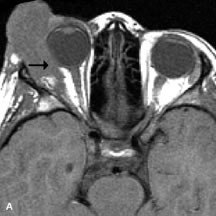

Inflammatory and Lymphoproliferative Lesions

Inflammatory conditions of the orbit, both idiopathic (inflammatory pseudotumor) and those of known causes, have been found to be hypointense to fat and isointense to muscle on Tl-weighted studies and isointense or slightly hyperintense to fat on T2-weighted images (Fig. 21).50,64,69 The more fibrous or sclerosing varieties have less signal intensity on T2-weighted images. Marked enhancement is seen in pseudotumor infiltrates after gadolinium administration.70 The same signal characteristics are demonstrated in patients with Tolosa-Hunt syndrome, with mass lesions seen in the cavernous sinuses and orbital apices.71

Fig. 21. A. T1-weighted MR scan demonstrates diffuse enlargement of both the superior rectus and levator palpebrae superioris muscles (single arrows). The involvement of the tendinous insertions and preseptal soft tissues (open arrows) as well as lack of involvement of other muscles helps differentiate this entity from thyroid-associated orbitopathy. B and C. Postcontrast fat-suppressed T1-weighted MR scans demonstrate extensive enhancement of the involved muscles as well as the preseptal (open arrows) and perinuscular tissues (double arrows).